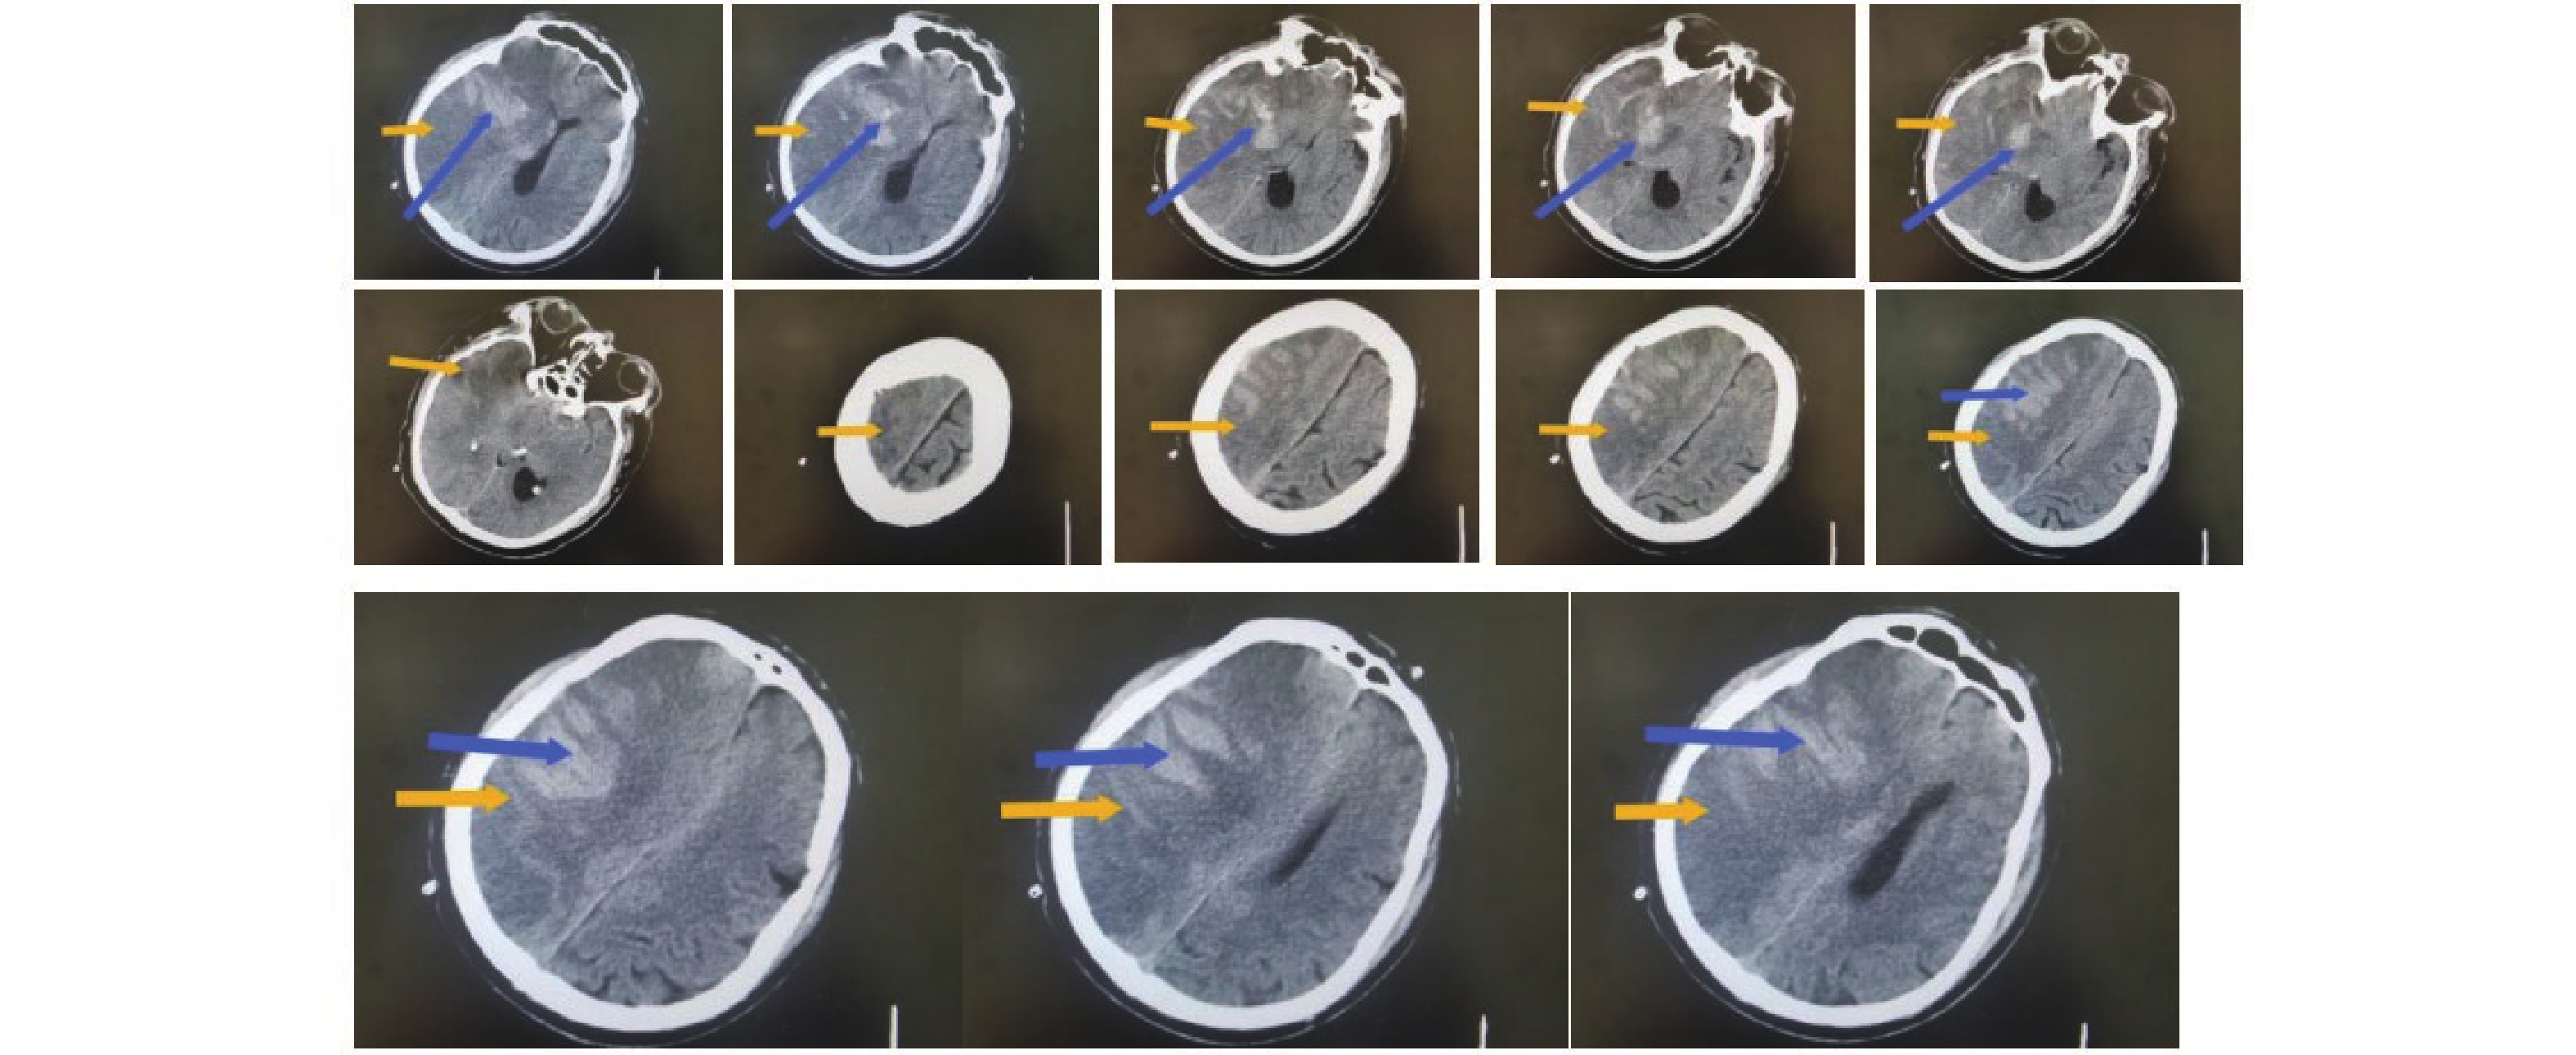

丁苯酞联合阿托伐他汀治疗脑梗死的疗效及对血管内皮vWF、PAI-1、VE-cadherin表达的影响

李克娇, 刘梓宸, 畅莎, 宋雪, 李芳

摘要(536) HTML(259) PDF (71)

摘要:

目的  分析丁苯酞联合阿托伐他汀治疗脑梗死的疗效及对血管内皮血友病因子(vascular endothelial hemophilia factor,vWF)、凝血酶原激活物抑制物-1(prothrombin activator inhibitor-1,PAI-1)、钙黏蛋白(Cadherin,VE-cadherin)表达的影响。  方法  选取2021年10月至2023年10月期间廊坊市第四人民医院收治的150例脑梗死患者随机盲法分组,各75例。对照组以阿托伐他汀治疗,试验组以丁苯酞联合阿托伐他汀治疗。对比两组疗效、脑部血流状态、斑块超声指标、斑块稳定性影像学指标、血管内皮功能指标、生活质量评分、治疗安全性等。  结果  试验组的总有效率90.67%高于对照组74.67%(P < 0.05)。治疗后,试验组血流动力学指标改善幅度高于对照组(P < 0.05)。治疗后,相较于对照组,试验组患者的颈动脉中膜厚度(IMT)、斑块厚度、斑块面积均更低(P < 0.05)。治疗后,相较于对照组,试验组的MRI检查指标包括纤维帽更高,脂质核心更低(P < 0.05)。治疗后,相较于对照组,试验组vWF、PAI-1、VE-cadherin表达水平均更低(P < 0.05)。对两组患者进行为期1年的随访观察,试验组脑卒中生活质量量表(quality of life scale for stroke,SS-QOL)各项评分均高于对照组(P < 0.05)。两组不良反应发生率对比差异无统计学意义(P > 0.05)。  结论  阿托伐他汀与丁苯酞联合治疗脑梗死成效显著,该疗法不仅有助于改善脑部血流状况,还能增强颈动脉粥样硬化斑块的稳定性,对血管内皮功能起到积极的改善作用,且安全性较高。